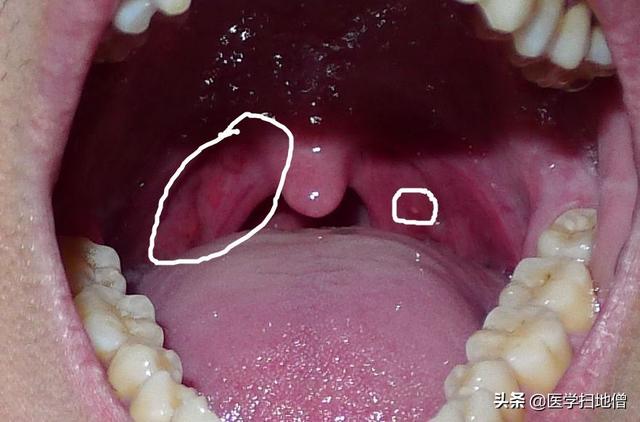

喉の異物感は通常、耳鼻咽喉科で診察されることが多いので、喉頭鏡検査は必須であり、検査で咽頭肥大、うっ血、リンパ濾胞過形成が認められれば、基本的に間違いない。慢性咽頭炎もし扁桃腺の肥大とうっ血が見られるなら、それは慢性扁桃炎.しかし、喉頭蓋の炎症だけが喉の異物感を引き起こすわけではない。副鼻腔炎、胃食道逆流症などまた、同様の臨床症状を引き起こすこともあるため、必要に応じて胃カメラ検査も行う。

喉の違和感に対して多くの人が最初に反応するのが咽頭炎である。慢性咽頭炎は確かに喉の違和感の最も重要な原因の一つである。慢性咽頭炎に罹患している人は、のどに異物感を感じたり、のどに違和感を感じたり、しばしば咳払いをしたりすることが多い。咽頭粘膜のうっ血、リンパ濾胞過形成などの診断がつけば、慢性咽頭炎である可能性が高い。

2) 慢性扁桃炎

咽頭の検査で、扁桃腺のうっ血、瘢痕化、陰窩の膿栓があれば、扁桃腺が慢性化していると判断できる。この病気はまた、のどの不快感を引き起こす。